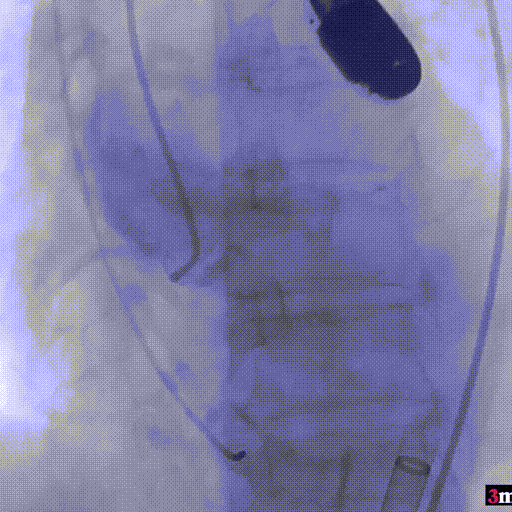

手术过程回顾:

患者全麻后,右侧股动脉建立主入路,主动脉根部造影显示主动脉瓣无明显钙化。心室内轻中量反流,主动脉及心脏情况整体较为稳定,根据术前策略预装23mm瓣膜。超硬置入左心室后,因超硬压迫无冠瓣叶导致急性反流,病人血压降至40mmHg,遂迅速将输送器送入主动脉根部,快速释放瓣膜后,病人血压恢复至正常。瓣膜脱钩后造影显示左冠开口存在一定狭窄,IVUS评估左冠开口狭窄约60%,符合PCI指征,植入开窗支架改善狭窄,最终再次造影加IVUS评估左冠开口,确定狭窄解除。

主动脉根部造影

输送器定位

完全释放后造影疑似左冠狭窄

IVUS探查左冠开口狭窄60%

放置开窗支架

球囊后扩支架

假体瓣膜形态良好,无明显瓣周漏

术后测量跨瓣压差仅为1mmHg